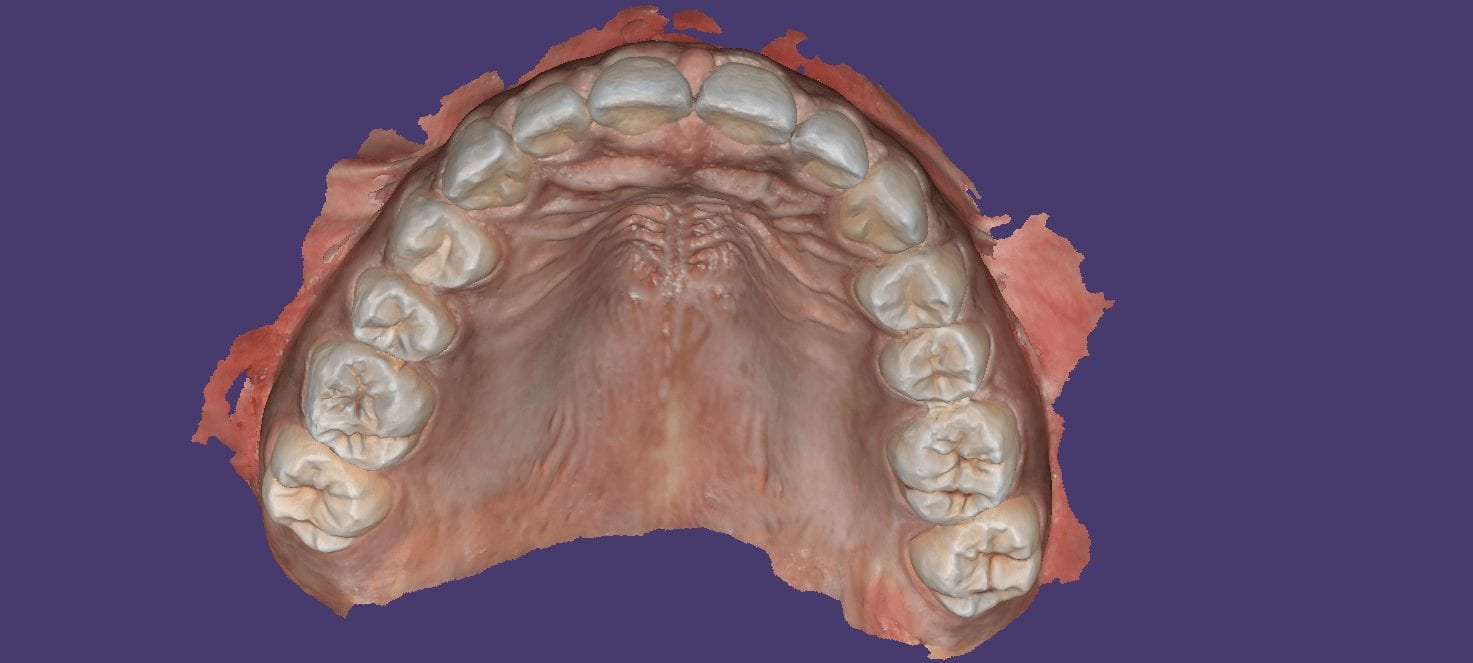

June 25, 2019This case shows the amount of control one can have over the fit of a restoration. The upper right first molar was imaged with the Medit i500 and then imported […]